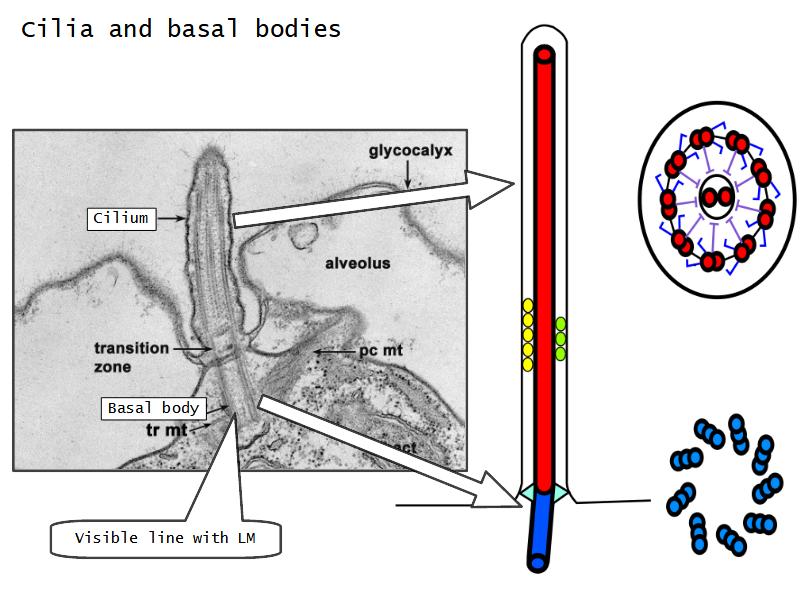

Respiratory epithelium

- Pseudostratified

- Ciliated

- Columnar

- Epithelium with

- 4 Cells

- Ciliated columnar cells

- Non-ciliated columnar cells

- Goblet cells

- Basal cells